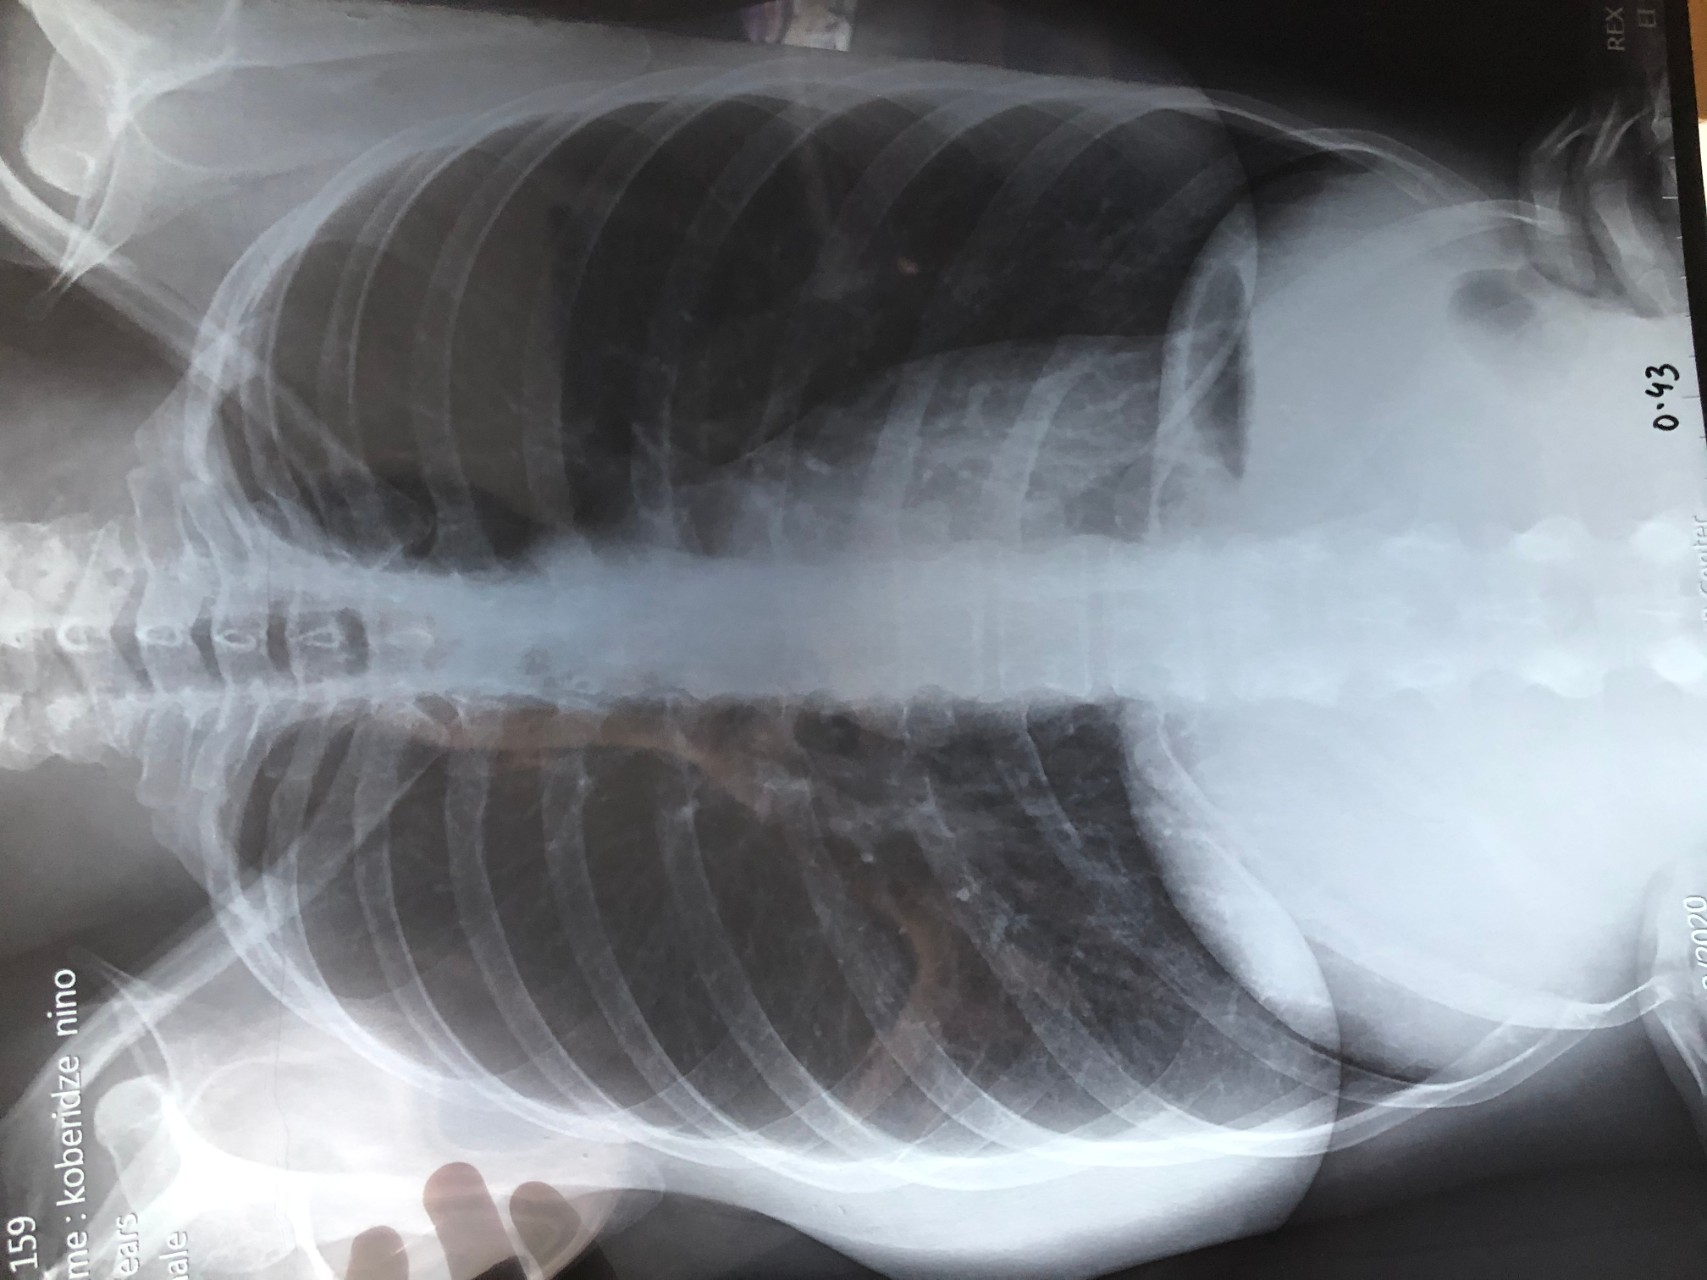

Фотографии, демонстрирующие обнаруженное усиление легочного рисунка

Раздел: Фотодневник открытий